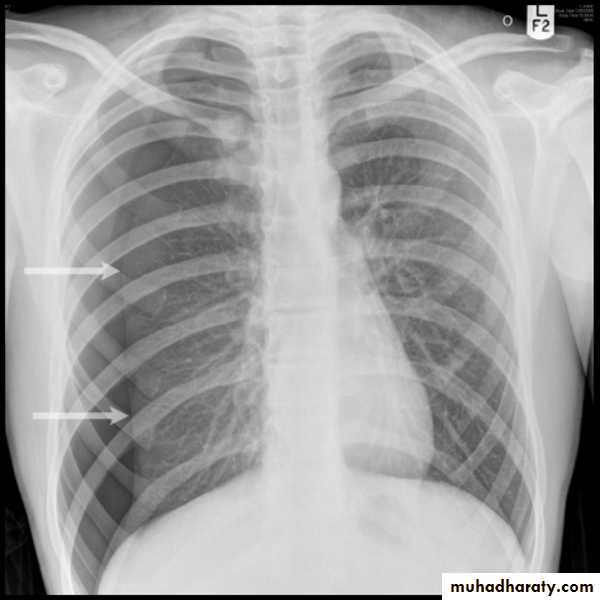

PneumothoraxX-ray pneumothorax

X-ray pneumothorax

X-ray tension pneumothorax